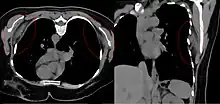

Bilateral elastofibroma dorsi in native computed tomography: left image axial in prone position (for biopsy), right image oblique coronal view. |

By computed tomography, there is a poorly circumscribed, heterogeneous soft tissue mass, with a signal intensity similar to skeletal muscle. The fact that the lesion may be bilateral, helps eliminate a sarcoma from further consideration.[5] At US, elastofibromas are depicted deep to the musculature as a multilayered pattern of hypoechoic linear areas of fat deposition intermixed with echogenic fibroelastic tissue.[6] The mass often protrudes from the subscapular region upon shoulder abduction, allowing better delineation of the finding.[7]